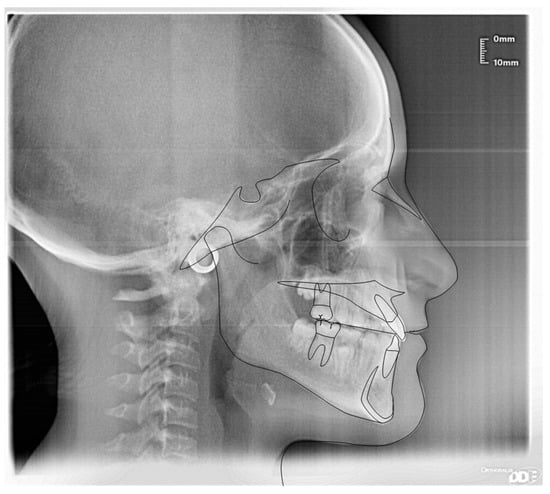

3.1. Clinical Case #1

| Cephalometric Analysis before Treatment | Val | Dev | Min | Med | Max | Diff |

|---|---|---|---|---|---|---|

| SNA | 82° | N | 80° | 82° | 84° | 0° |

| SNB | 78.6° | N | 78° | 80° | 82° | 0° |

| ANB | 3.4° | N | 0° | 2° | 4° | 0° |

| sna-snp^Go-Gn | 22.3° | N | 15° | 20° | 25° | 0° |

| S-N^sna-snp | 8.9° | N | 7° | 10° | 13° | 0° |

| S-N^PO | 14.2° | N | 11° | 14° | 17° | 0° |

| S-N^Go-Gn | 31.2° | N | 27° | 32° | 37° | 0° |

| SNBa | 136.6° | x | 124° | 129° | 134° | 2.6° |

| SND | 75.1° | N | 74° | 76° | 78° | 0° |

| IS^II | 128.9° | N | 125° | 130° | 135° | 0° |

| IS:N-A | 3.5 | N | 3 | 4 | 5 | 0 |

| II:N-B | 3.7 | N | 3 | 4 | 5 | 0 |

| II:A-Pog | 1.7 | N | −1 | 1 | 3 | 0 |

| Ls:Line S | −2.1 | −xx | −1 | 0 | 1 | 1.1 |

| Li: Line S | 0.4 | N | −1 | 0 | 1 | 0 |

| Cvm:S-Gn | −3.4 | −xxx | −1 | 0 | 1 | 2.4 |

| Mol Sup^P. Occl | 99.5° | xxxx | 88° | 90° | 92° | 7.5° |

| N-S-Cop | 135.2° | xx | 117° | 122° | 127° | 8.2° |

| S-Cop-Go | 137.3° | N | 137° | 143° | 149° | 0° |

| Cop-Go-Gn | 118.7° | N | 115° | 120° | 125° | 0° |

| Cop-Go-N | 51.2° | N | 48° | 50° | 52° | 0° |

| N-Go-Gn | 67.6° | −x | 68° | 70° | 72° | 0.4° |

| II^Go-Gn | 94.1° | x | 92° | 93° | 94° | 0.1° |

| SOr:sna | 62.9 | 0 | 0 | 0 | 62.9 | |

| sna:Me | 63.7 | 0 | 0 | 0 | 63.7 | |

| S:N | 69.6 | −xx | 75 | 78 | 81 | 5.4 |

| snp:A | 54.7 | 0 | 0 | 0 | 54.7 | |

| Go:Me | 75.4 | N | 73.7 | 78.7 | 83.7 | 0 |

| Wits | 1.5 | N | −2 | 0 | 2 | 0 |

| IS^N-S | 105.9° | x | 101° | 103° | 105° | 0.9° |

| Pog:N-B | 0.9 | 0 | 0 | 0 | 0.9 | |

| Pog:N-B—II:N-B | −2.8 | - | 0 | 0 | 0 | 2.8 |

| Cephalometric Analysis after Treatment | Val | Dev | Min | Med | Max | Diff |

| SNA | 81.8° | N | 80° | 82° | 84° | 0° |

| SNB | 78.9° | N | 78° | 80° | 82° | 0° |

| ANB | 2.9° | N | 0° | 2° | 4° | 0° |

| sna-snp^Go-Gn | 22.4° | N | 15° | 20° | 25° | 0° |

| S-N^sna-snp | 9.1° | N | 7° | 10° | 13° | 0° |

| S-N^PO | 12.4° | N | 11° | 14° | 17° | 0° |

| S-N^Go-Gn | 31.5° | N | 27° | 32° | 37° | 0° |

| SNBa | 139.7° | xx | 124° | 129° | 134° | 5.7° |

| SND | 76.1° | N | 74° | 76° | 78° | 0° |

| IS^II | 125.1° | N | 125° | 130° | 135° | 0° |

| IS:N-A | 3.8 | N | 3 | 4 | 5 | 0 |

| II:N-B | 4.4 | N | 3 | 4 | 5 | 0 |

| II:A-Pog | 2.2 | N | −1 | 1 | 3 | 0 |

| Ls:Line S | −3 | −xxx | −1 | 0 | 1 | 2 |

| Li: Line S | 1.2 | x | −1 | 0 | 1 | 0.2 |

| Cvm:S-Gn | −4.7 | −xxxx | −1 | 0 | 1 | 3.7 |

| Mol Sup^P. Occl | 95.2° | xx | 88° | 90° | 92° | 3.2° |

| N-S-Cop | 132.3° | xx | 117° | 122° | 127° | 5.3° |

| S-Cop-Go | 143.9° | N | 137° | 143° | 149° | 0° |

| Cop-Go-Gn | 115.3° | N | 115° | 120° | 125° | 0° |

| Cop-Go-N | 49.4° | N | 48° | 50° | 52° | 0° |

| N-Go-Gn | 66° | −xx | 68° | 70° | 72° | 2° |

| II^Go-Gn | 93.4° | N | 92° | 93° | 94° | 0° |

| SOr:sna | 72.3 | 0 | 0 | 0 | 72.3 | |

| sna:Me | 67.3 | 0 | 0 | 0 | 67.3 | |

| S:N | 72.9 | −x | 75 | 78 | 81 | 2.1 |

| snp:A | 56.1 | 0 | 0 | 0 | 56.1 | |

| Go:Me | 86.4 | x | 73.7 | 78.7 | 83.7 | 2.7 |

| Wits | 2 | N | −2 | 0 | 2 | 0 |

| IS^N-S | 109.9° | xxx | 101° | 103° | 105° | 4.9° |

| Pog:N-B | 1.5 | 0 | 0 | 0 | 1.5 | |

| Pog:N-B—II:N-B | −2.9 | - | 0 | 0 | 0 | 2.9 |